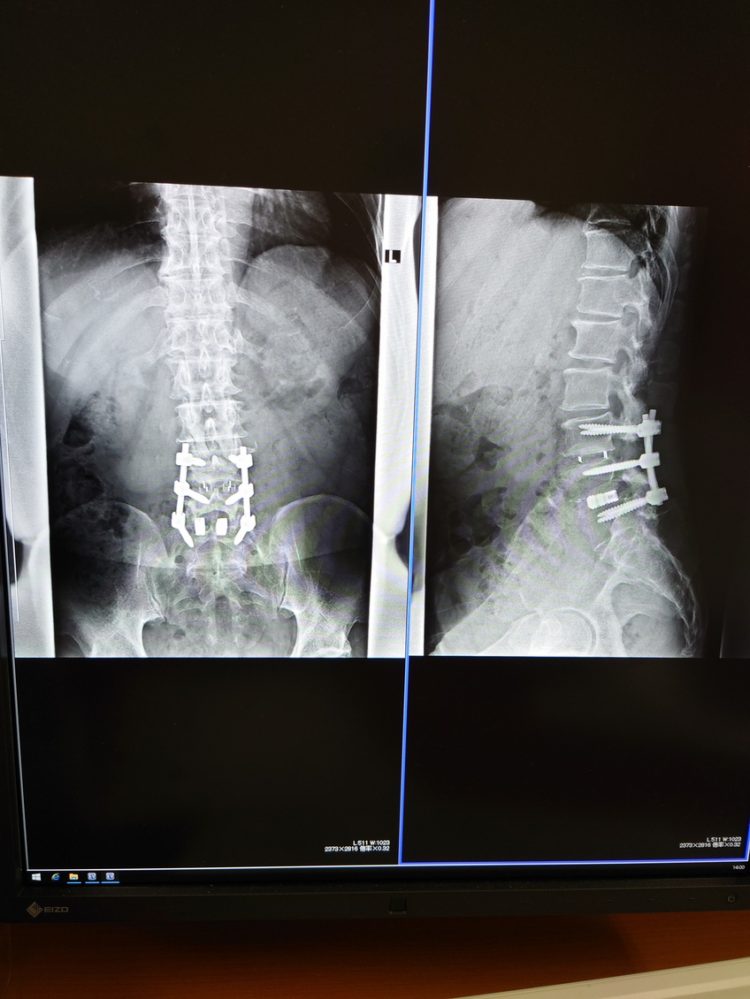

これをなんと名付けようか?サイボーグ北村?ロボコップ北村。。。史上最強の腰?脊髄?この身体で7月4週に渡り仙台、お盆明けもコロナ終息を願いながら挨拶回りです。この写真が結構~話のネタになるんですよ(^_-)-☆